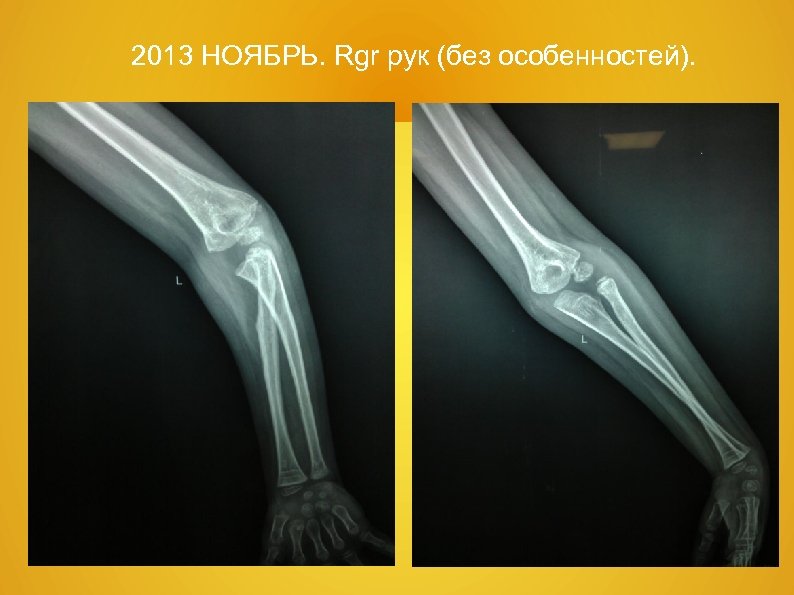

2013 НОЯБРЬ. Rgr рук (без особенностей).